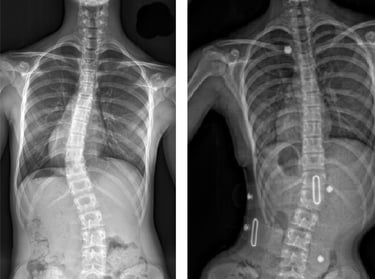

Scoliosis is often first noticed by parents or close family members, as the shoulders or pelvis may appear uneven. A thorough physical examination is conducted to assess posture, gait, and spinal alignment. The Adams Position Test, which involves the patient bending forward to reveal any visible curvature, is commonly used to assess scoliosis. If a noticeable curve is detected, an X-ray is typically ordered to determine the severity of the condition.